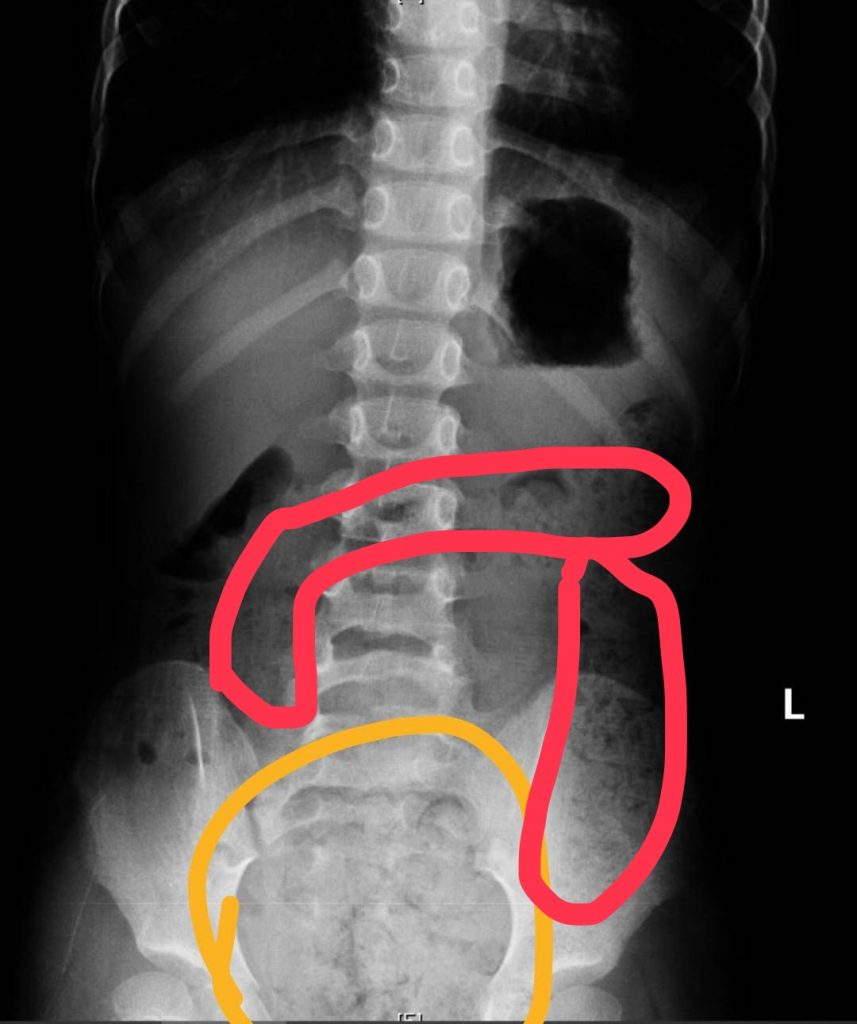

真的會有「一肚子的大便」!一名11歲小五男生因為腹痛、冒冷汗、嘴唇發紫、手腳冰冷被送來急診,經問診、觸診及腹部X光檢查後診斷是便秘,為他灌腸後解出很多大便,症狀也隨即緩解,媽媽說男孩習慣邊大便、邊玩手機,也都不清楚是否有大出來或有沒大乾淨;另一名6歲女孩除了肚子痛得直哭叫,腹部並明顯異常脹大,經腹部X光檢查發現她「一肚子大便」,媽媽說她可能剛上小學,還沒習慣上課節奏,有便意也忍著不去廁所,就連幾天沒上大號也記不清,直到症狀嚴重掛急診。